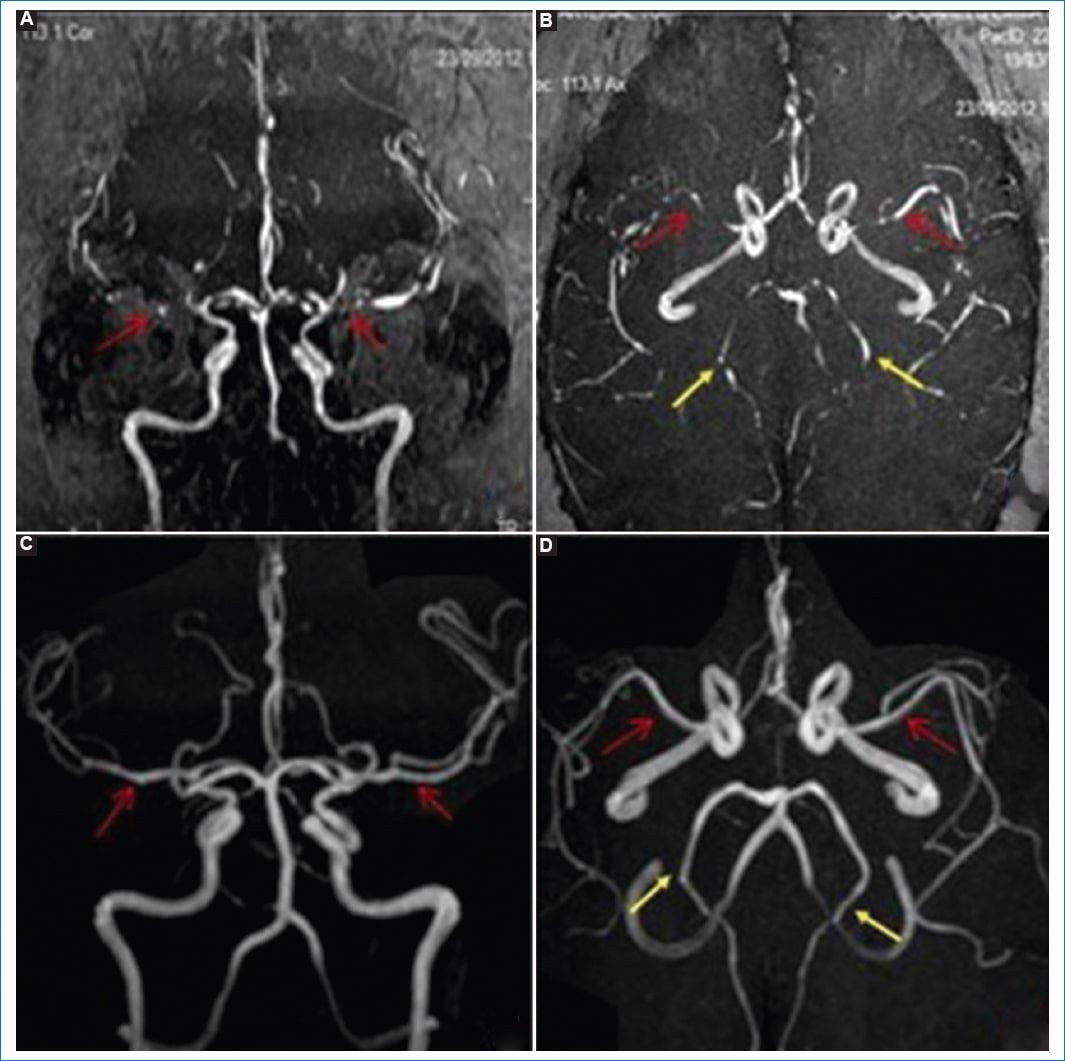

• RM: puede haber áreas con edema vasogénico representadas por hiperintensidad en T2 e hipointensidad en T1. Puede haber áreas de HSA. La angio-RM o la angio-TC demuestran estrechamientos vasculares multifocales en forma difusa que se suelen resolver a los tres meses (Fig. 3)4.

• Angiografía: se observan estenosis multifocales reversibles de los vasos de segundo y tercer orden de la circulación anterior y posterior. Puede persistir durante días y semanas, y en caso de progresar puede asociarse a estenosis de vasos más proximales (va de distal a proximal). Los estudios realizados en una fase temprana no suelen documentar alteraciones, dado que la máxima vasoconstricción de las ramas de la arteria cerebral media se documenta alrededor de los 16 días después del inicio clínico4,17.

Figura 3. Síndrome de vasoconstricción cerebral reversible. Secuencias de angio-RM intracraneal. (A y B) Se observa estrechamiento de la arteria cerebral media de ambos lados en sus segmentos M1 y M2 (flechas rojas), y en menor medida afectación de las cerebrales posteriores de ambos lados (flechas amarillas). Posterior al tratamiento (C y D) se observan adecuada señal y calibre del circuito arterial anterior (flechas rojas) y posterior (flechas amarillas).